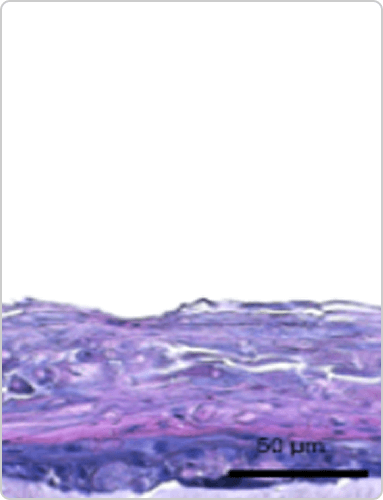

인체화 피부 모델(RHS) 평가

• TNF-α / IL-4 / IL-13으로 유도된 AD 표피 비후 모델에서 BSP011 처리 시 표피 비후가 정상 대조군 수준으로 회복

• Contorl

• AD cocktail

• AD cocktail + Dup*****

• AD cocktail + BSP011